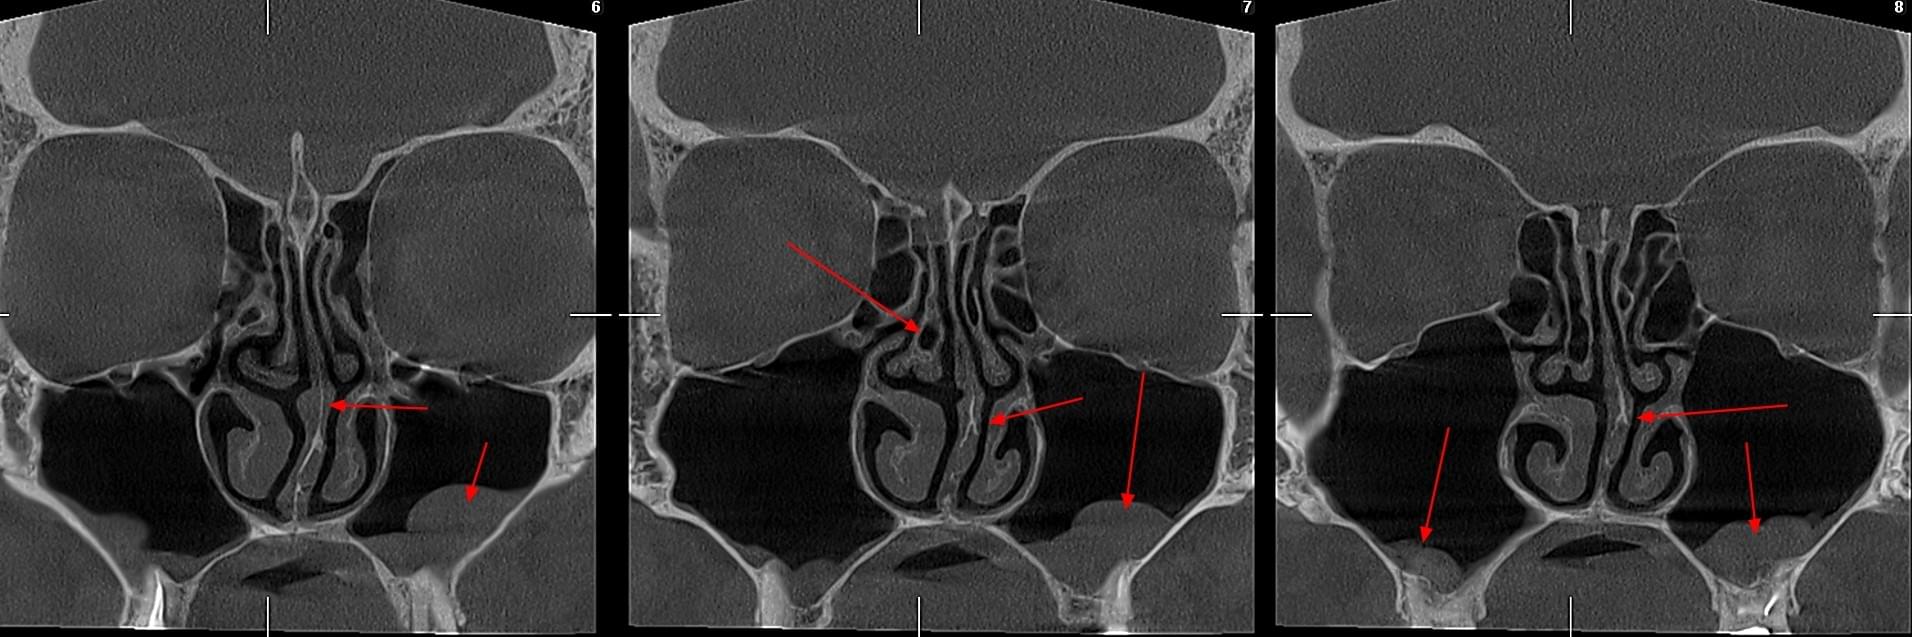

Діагностика гайморових пазух за допомогою КТ

У сучасній медицині КТ придаткових пазух носа (або КТ синусів) — це «золотий стандарт»

діагностики для ЛОР-лікарів та щелепно-лицевих хірургів. Звичайний рентген часто не

показує повну картину, а МРТ не завжди доступний і дорожчий. Комп’ютерна томографія дає

детальну 3D-модель усіх пазух (гайморових, лобних, клиновидних та решітчастого

лабіринту) за 10 секунд і з мінімальною дозою опромінення.

КПКТ (конусно-променева комп’ютерна томографія) — це 3D-знімок високої роздільної здатності. На відміну від звичайного рентгену, КТ показує: